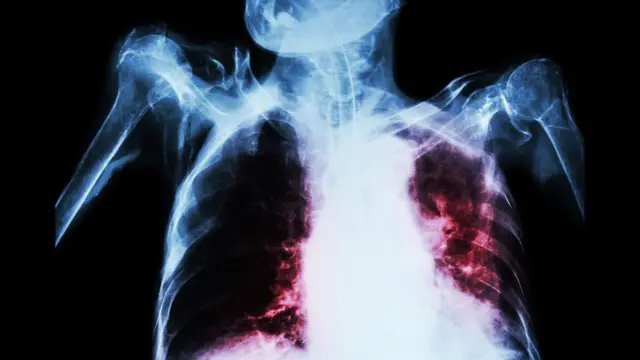

प्यूठान अस्पतालमा हेमोडायलाईसिस र एसएनसीयु उद्घाटन     |     होटल व्यवसायी संघ प्यूठानको स्थापना दिवसमा रक्तदान कार्यक्रम सम्पन्न     |     आफुखुसी गर्भपतनको औषधी सेवन गर्दा प्यूठानमा महिलाको झण्डै गयो ज्यान     |     विश्व क्षयरोग दिवस: नेपालमा बढ्दै नयाँ संक्रमित     |     सेतीमा दैनिक सेवा लिने बिरामीको सङ्ख्या बढ्दै     |     ‘अस्पतालले दिने सेवामा सर्वसाधारणको सहज पहुँच आवश्यक’     |     मौसम धुम्म हुञ्जेल प्रदूषण बढ्ने, सचेत रहन आग्रह     |     बाजुराकी एक महिलालाई बाटोमै गराइयो प्रसुति     |     नेपाल कम्युनिस्ट पार्टी (एकीकृत मार्क्सवादी–लेनिनवादी) को घोषणापत्र सार्वजनिक : स्वास्थ्य सेवा निःशुल्क र सर्वसुलभ बनाउने…     |     पाँच स्थानीय तहमा ‘सामुदायिक नर्सिङ तथा घरदैलो’ कार्यक्रम     |